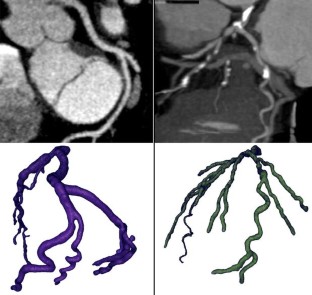

The purpose of this paper was to non-invasively assess hemodynamic parameters such as mass flow, wall shear stress (WSS), and wall pressure with computational fluid dynamics (CFD) in coronary arteries using patient-specific data from computed tomography (CT) angiography. Five patients (two without atherosclerosis, three with atherosclerosis) underwent retrospectively electrocardiogram (ECG) gated 16-detector row CT using ECG-pulsing and geometric models of coronary arteries were reconstructed for CFD analysis. Blood flow was considered laminar, incompressible, Newtonian, and pulsatile. The mass flow, WSS, and wall pressure were quantified and flow patterns were visualized. The wall pressure continuously decreased towards distal segments and showed pressure drops in stenotic segments. In coronary segments without atherosclerotic wall changes, WSS remained low, even during phases of high flow velocity, whereas in atherosclerotic vessels, the WSS was elevated already at low flow velocities. Stenoses and post-stenotic dilatations led to flow acceleration and rapid deceleration, respectively, including a distortion of flow. Areas of high WSS and high flow velocities were found adjacent to plaques, with values correlating with the degree of stenosis. CFD provided detailed mass flow measurements. CFD analysis is feasible in normal and atherosclerotic coronary arteries and provides the rationale for further investigation of the links between hemodynamic parameters and the significance of coronary stenoses.

Fig. 1

Fig. 2

Fig. 3

Fig. 4